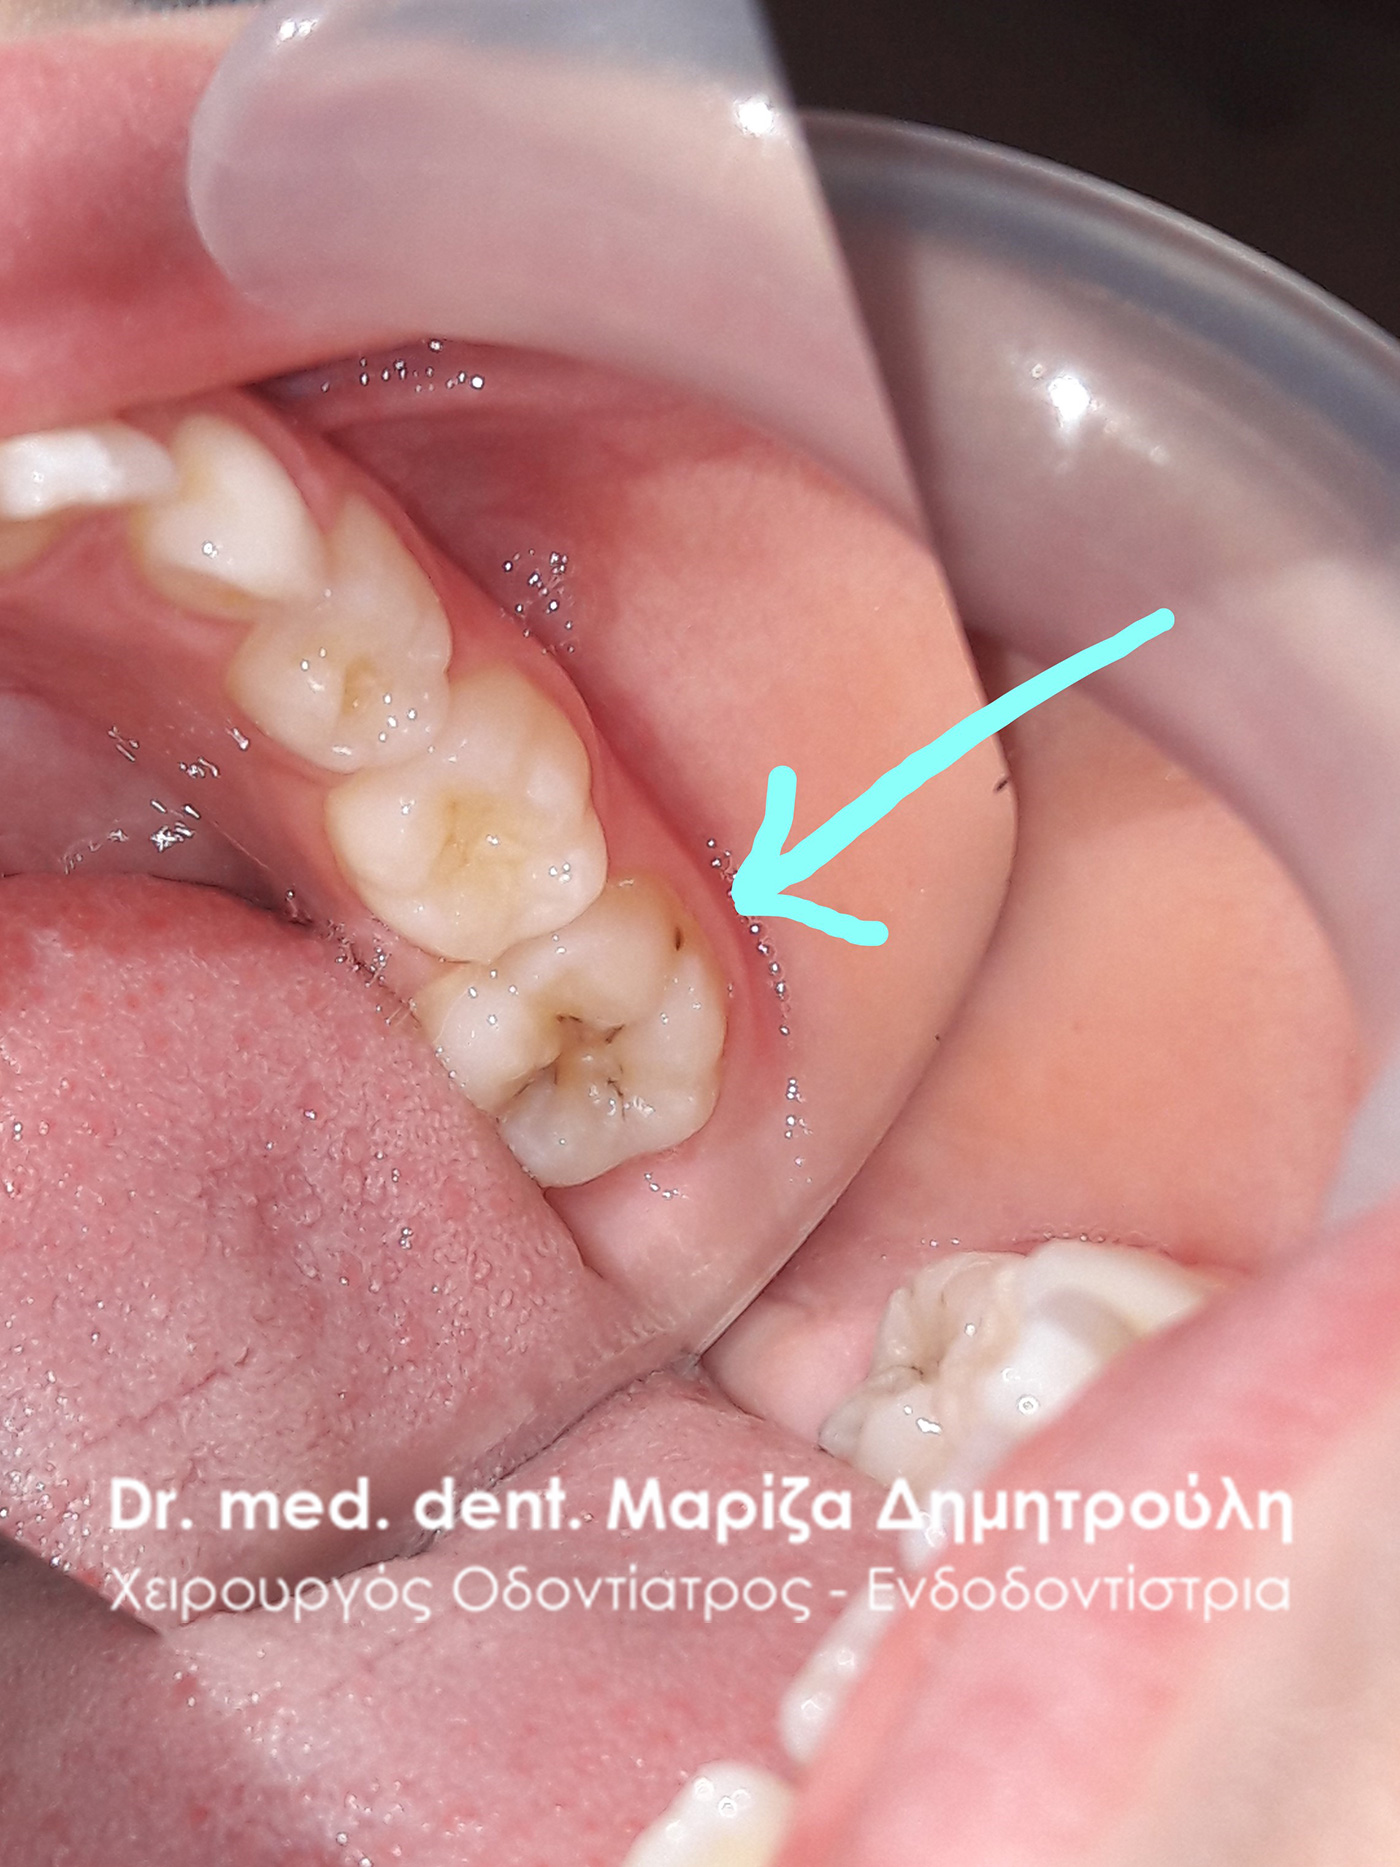

Περιστατικό – Σφραγίσματα παιδικών δοντιών

Κορίτσι ηλικίας 9 ετών αναφέρει οτι πονάει στην πάνω αριστερή πλευρά του στόματος της όταν μασάει. Μετά την κλινική εξέταση διαπιστώθηκε η ύπαρξη 2 τερηδονισμένων δοντιών. Στον πρώτο μόνιμο αριστερό γομφίο είναι εμφανής η ύπαρξη τερηδόνας, της οποίας η έκταση αποδείχτηκε αρκετά βαθιά κατά τη διάνοιξη του δοντιού. Στο δεύτερο νεογιλό (παιδικό) γομφίο παρατηρήθηκε η ύπαρξη τερηδονικής κοιλότητας μεσαίου βάθους.

Μετά την απομάκρυνση της τερηδόνας από τα δύο δοντάκια πραγματοποιήθηκαν λευκά σφραγίσματα σύνθετης ρητίνης.

ΠΡΙΝ

ΜΕΤΑ